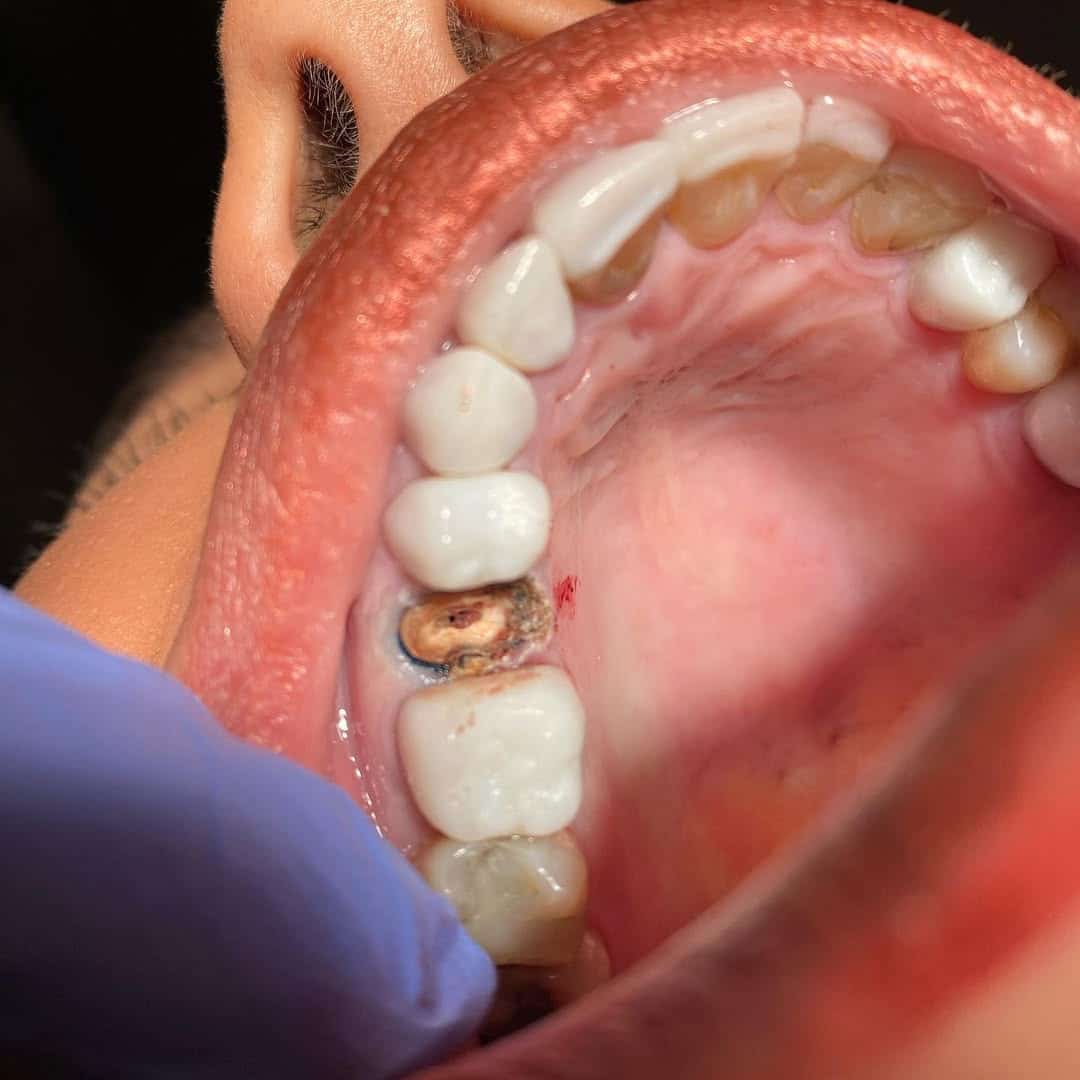

- Dolgu malzemesi ile tedavi edilemeyecek büyüklükte doku kaybı olan dişlerde

- Kanal tedavisi nedeniyle kırılgan hale gelen dişlerin korunmasında,